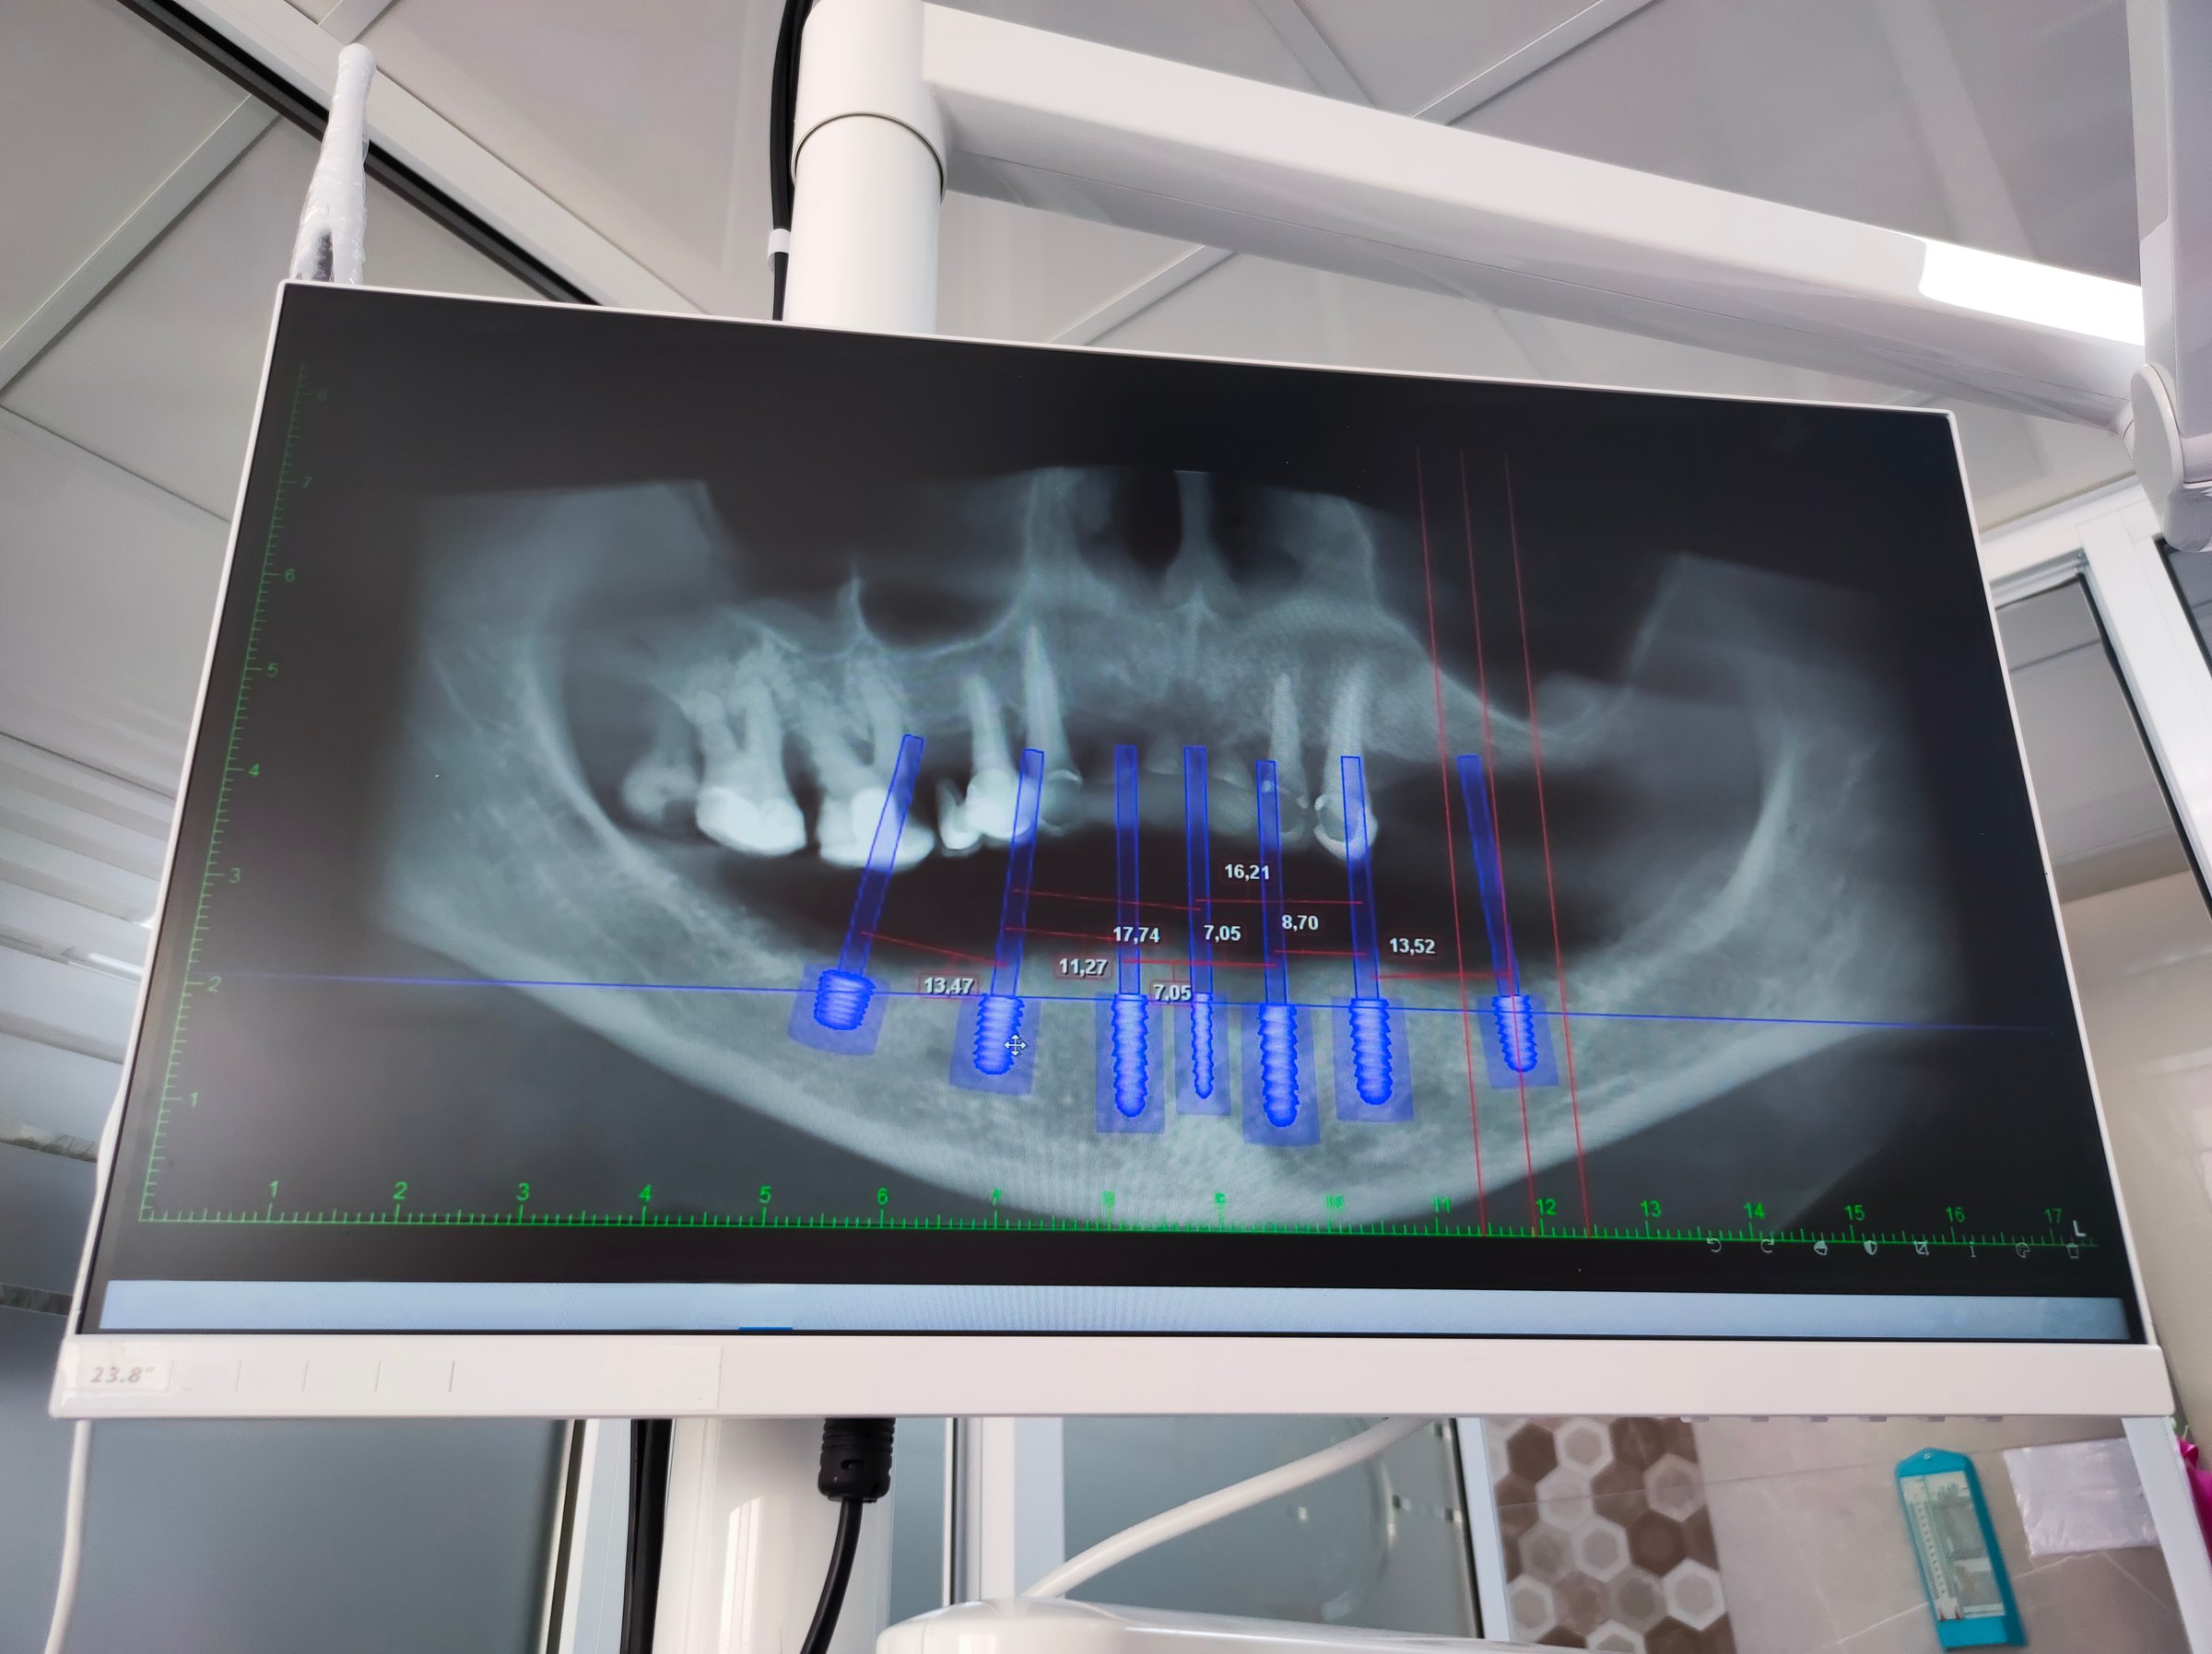

Dentist shows an X-ray of jaw with an implanted tooth. Dentist services

January 30, 2026 7 mins read

Anesthesia for Dental Implants: What to Expect, Options & Safety

Learn about the different anesthesia options for dental implants, what to expect during your procedure, and how we ensure your comfort and safety.